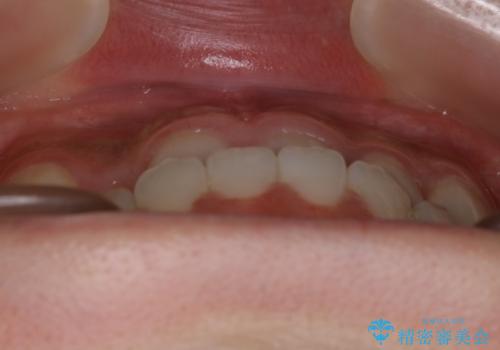

- 受け口の改善と前歯のガタつきの治療を主訴にご来院されました。

こちらの患者様の場合、上の前歯のガタつきが原因で口を閉じる際に上下の前歯の先端同士が先に当たってしまい、そこからさらに深く噛み込もうとすると下顎が前にずれていってしまうという、機能性の反対咬合であることが検査の結果わかりました。

そのため、まずは上顎の前歯のガタつきを改善していき、前歯が先に当たってしまうという症状を改善し噛み込む位置を後方の本来の位置に誘導する方法をとりました。